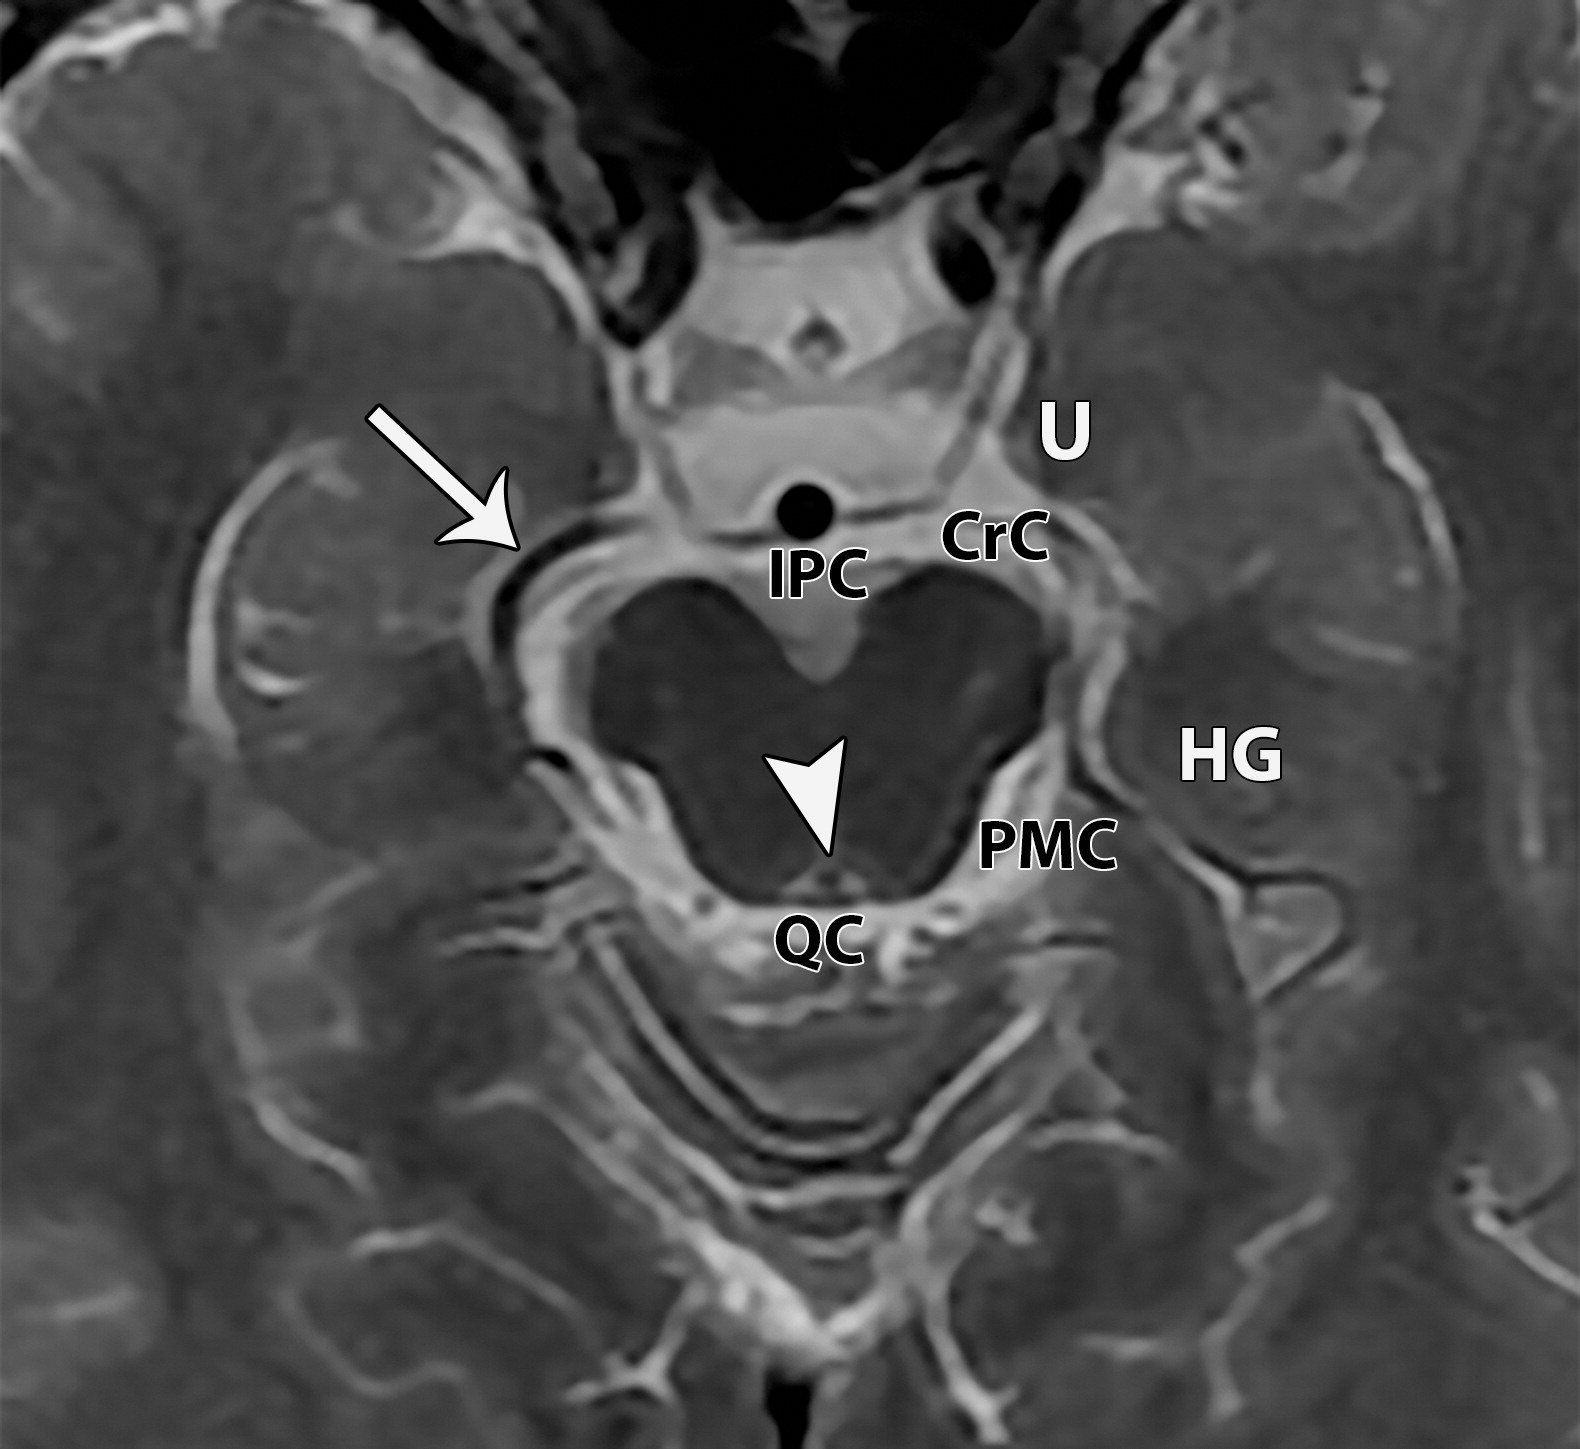

338eacde522c534fcbe30a562cfb64f4.jpeg

中脑导水管(白色短箭头),大脑后动脉(白色长箭头),大脑脚池(CrC),海马回(HG),大脑脚间池(IPC),中脑周围池(PMC),四叠体池(QC),钩回(U)。